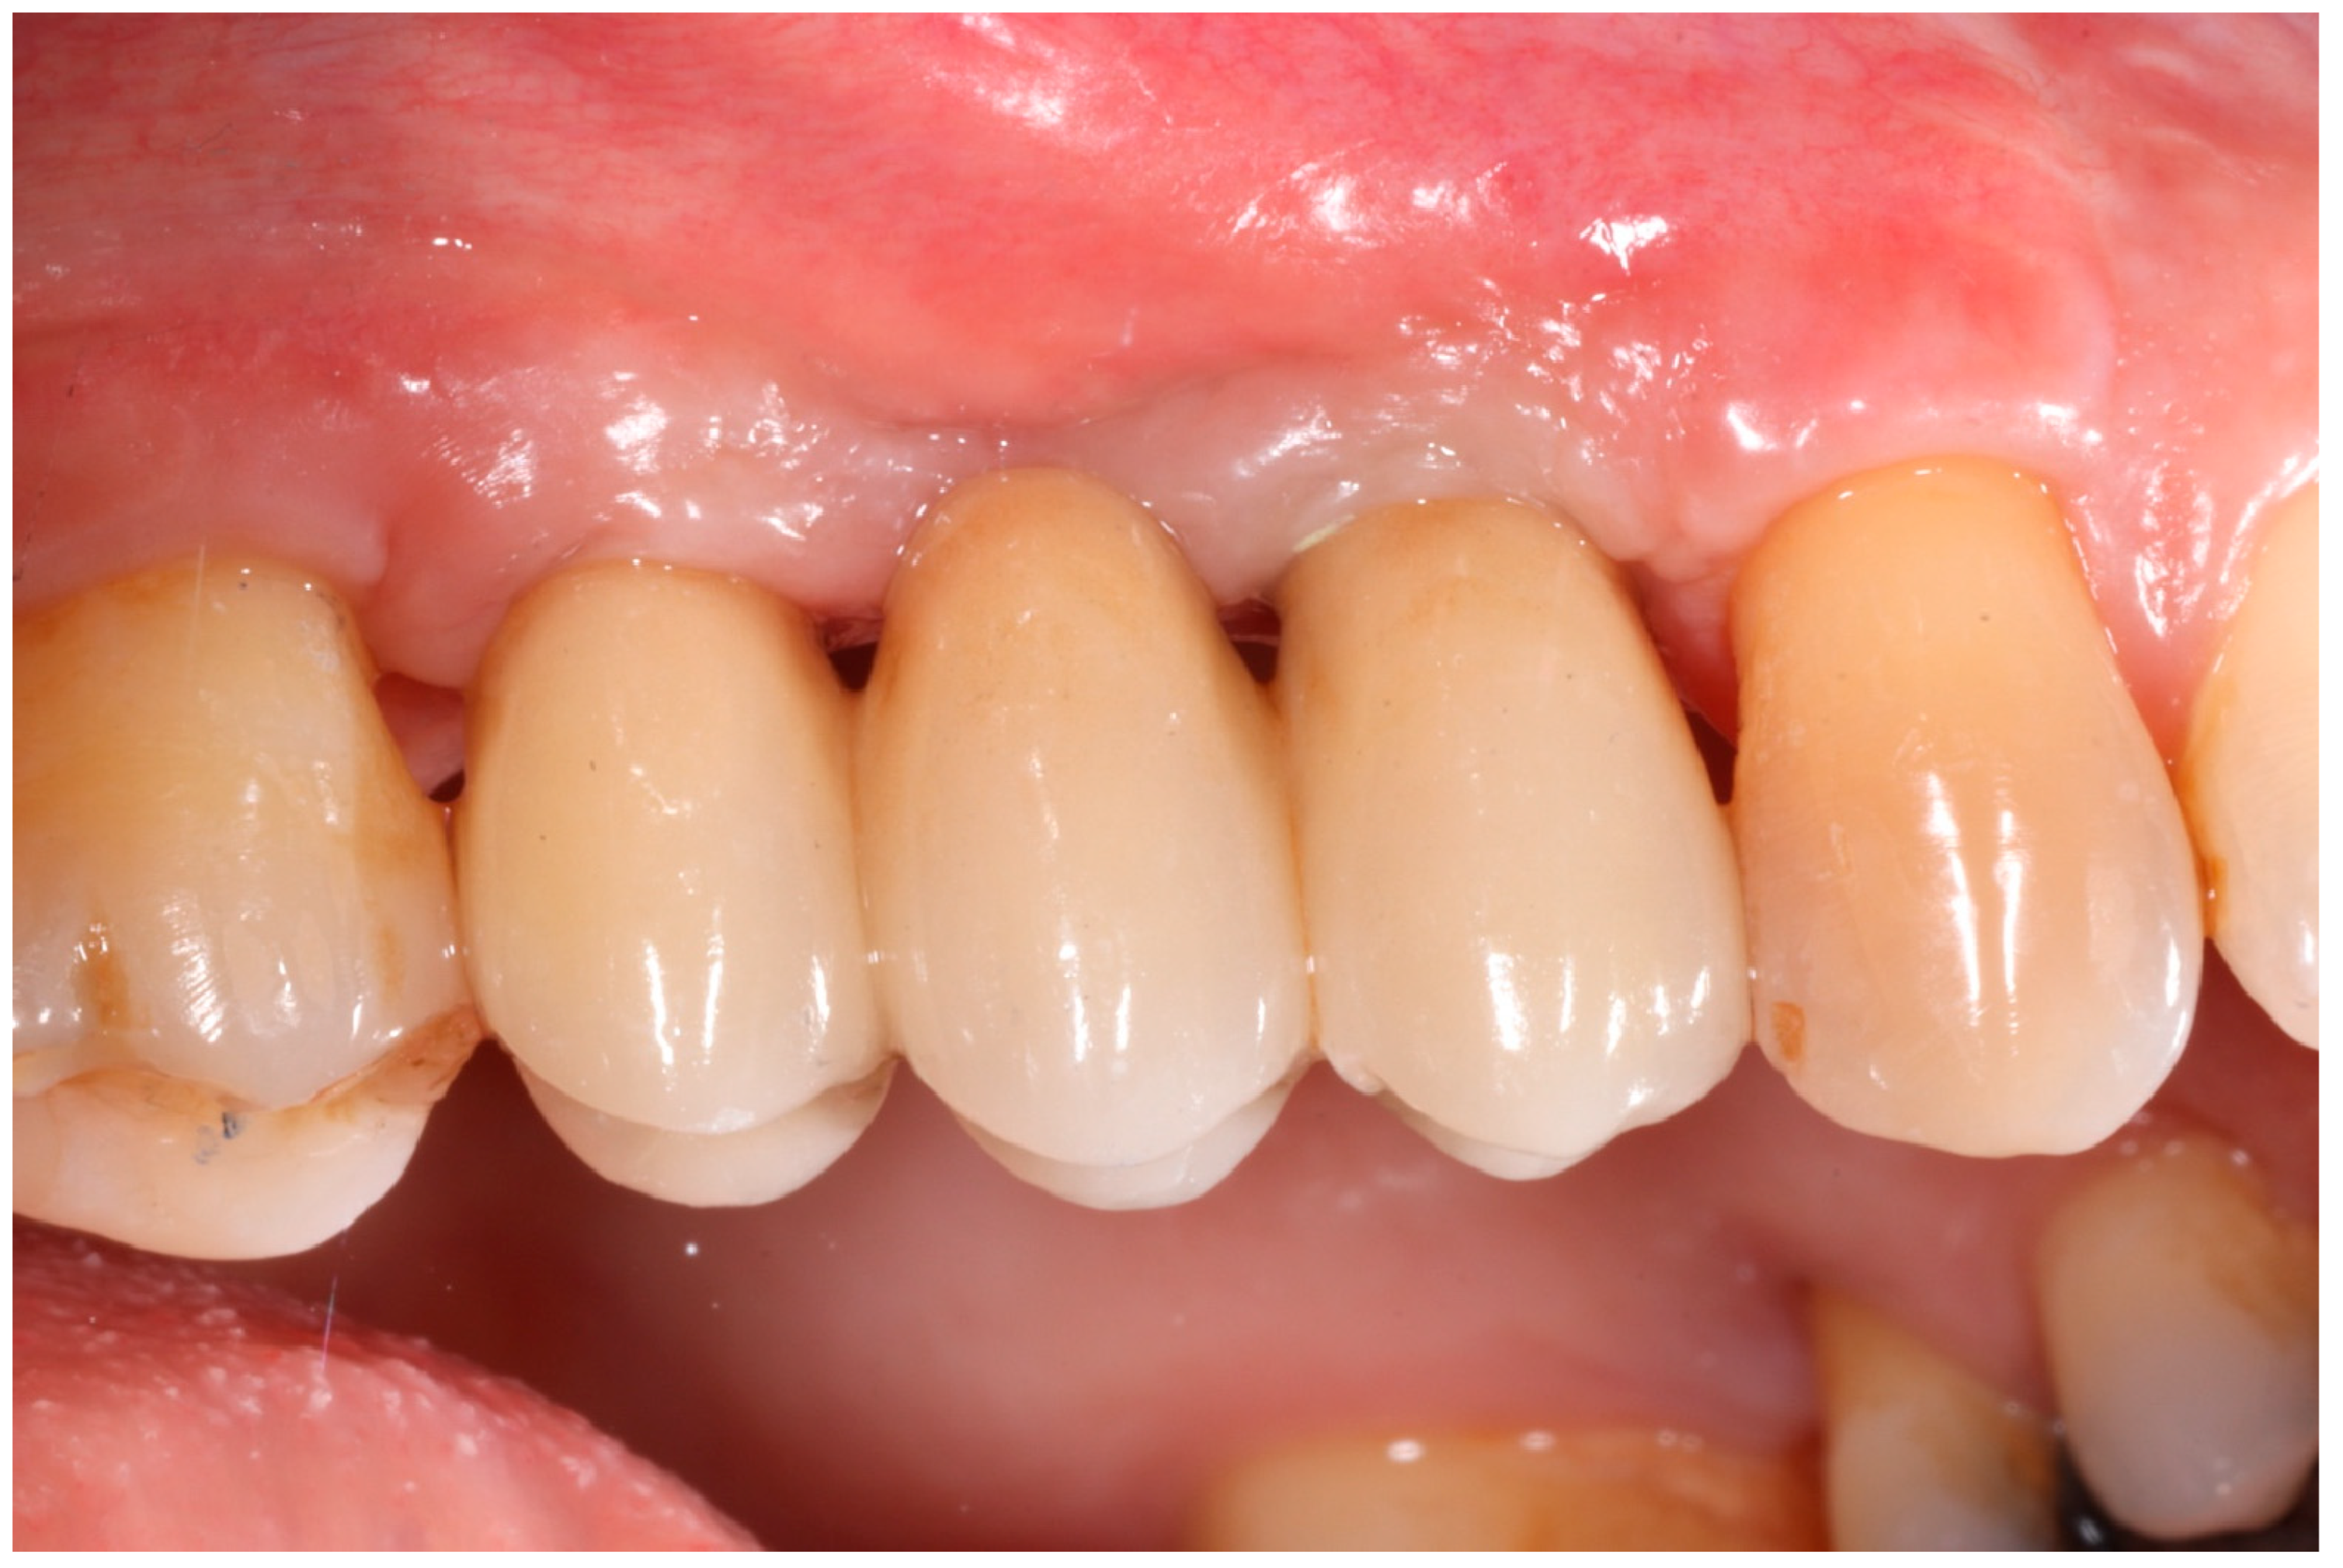

Healing abutments were screwed to the implants and the flaps were sutured. Additional peri-implant plastic surgery procedures (connective tissue grafts or free gingival grafts) were performed when needed in order to have at least 2 mm of attached keratinized mucosa. The prosthetic phases began upon healing of the soft tissues, and definitive screw-retained prostheses were finally delivered (Figure 11, Figure 12 and Figure 13).

Figure 11.

Delivery of definitive prosthesis.